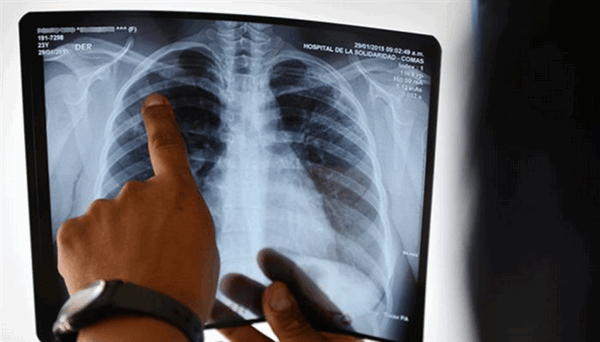

МРТ при туберкулезе

Снимок грудной клетки

Туберкулез - опасное заболевание, которое при несвоевременной диагностике имеет неблагоприятный прогноз. Раннее обследование патологий легких играет важную роль в проведении эффективного лечения. Первым методом, к которому прибегают врачи при подозрении на туберкулез легких или при профилактических осмотрах, является рентгенография.

Компьютерную и магнитно-резонансную томографию используют в качестве дополнительных вариантов обследования для определения расположения патологического очага, его размера и степени воспалительного процесса. Сравнивая КТ и МРТ, первый способ диагностики обладает более широкими возможностями выявления любых форм туберкулеза. МРТ при вышеупомянутом заболевании легких помогает дифференцировать патологию от других недугов: злокачественной и доброкачественной опухолей, воспалительных, паразитарных патологий и пр.

При положительном кожном тесте, фтизиатр назначает пациенту флюорографию грудной клетки, рентгенографию или компьютерную томографию. Данные процедуры могут выявить белые пятна в легких - области, где иммунная система оградила бактерии туберкулеза. Кроме того, будут выявлены конкретные изменения в легких, вызванные активным туберкулезом.

Если рентген грудной клетки выявил признаки туберкулеза, то врач может отобрать образцы мокроты — слизи, которая выделяется при кашле. Образцы исследуются на наличие бактерий туберкулеза. Образцы мокроты также можно использовать для тестирования на лекарственно-устойчивые штаммы туберкулеза. Это позволит врачу выбрать лекарства, которые с большей вероятностью окажут медикаментозный эффект. Получение результатов этих исследований может занять от 4 до 8 недель.

Рентгенография органов клетки является первичным методом диагностики туберкулеза. Ее данные позволяют установить факт болезни, провести дифференциальную диагностику туберкулеза от пневмонии, абсцесса и опухоли. Цифровая рентгенография позволяет определить характер поражения ткани легких (инфильтративный, очаговый, диссеминированный, кавернозный туберкулез) и локализацию очагов. Первичные признаки ТБ включают наличие очага или их группы в легких и увеличение лимфоузлов.